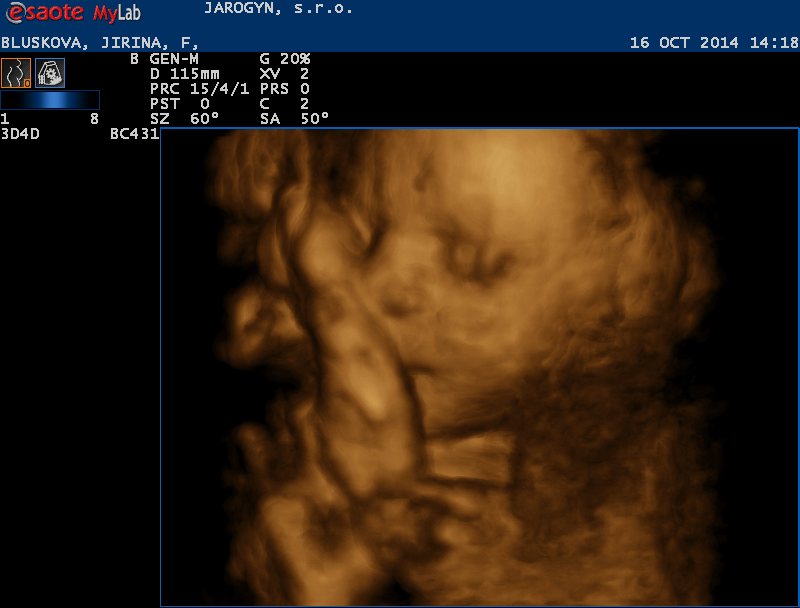

Ahoj holky tak jsem všera cestovala a utrácela a mám skoro všechno. Koupila jsem přebalovací podložku cestovní, látkové plínky, odsávačku hlenů, teploměr do vody, čepičku a rukavičky. a pak hurá na 4D ultrazvuk kde mě mordovala 45 minut mimisko si pořád rávalo ručičky před obličej nebo si hrálo s pupeční šňůrou. Přikládám fotečky.

Jiřinko,ty jsi ale nákupní maniačka.....a snímky ze 4Dultrazvuku,ty nemají chybu....že by holčička? Naše Marjánka si taky kryla před námi obličej. Tobě asi není souzeno znát pohlaví mimča,když tě manžel neustále provází....hold to bude překvápko,jak jste plánovali od začátku